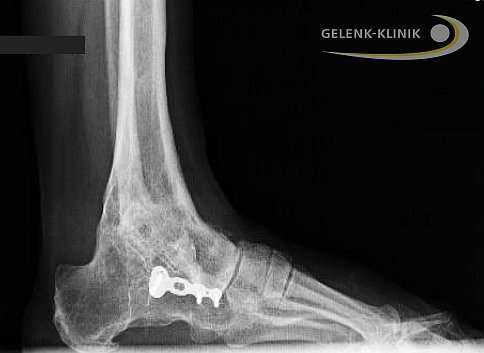

Артродез голеностопного сустава проводится и при использовании интрамедуллярных гвоздей, которые соединяют большеберцовую кость с таранной и пяточной. Артроз нижнего голеностопа и тяжелые травмы пяточной кости требуют проведения данной методики. Применение интрамедуллярных гвоздей для обездвиживания голеностопа приводит ещё и обездвиживанию сустава между пяточной и таранной костью. © Gelenk-Klinik